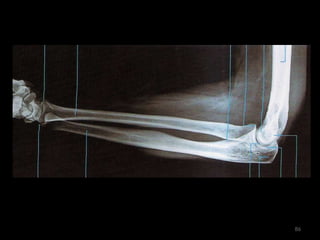

antebraço80

Incidência AP/PA do antebraço81

82

83

Incidência lateral do antebraço: látero-medial84

85

86

Punho, mão e dedos87